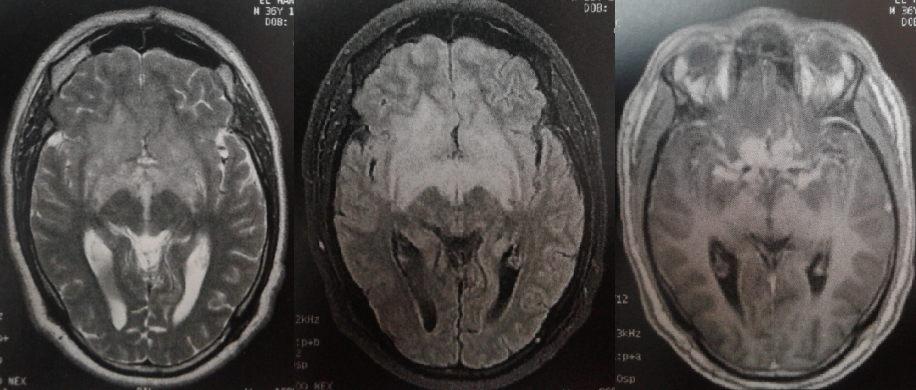

Nous rapportons l´observation d´un patient de 37 ans qui présenta une neuropathie optique droite. L´imagerie par résonnance magnétique (IRM) révéla la présence d´un hypersignal T2 de la ligne médiane rehaussé après injection de gadolinium. L´examen du liquide céphalo-rachidien (LCR) retrouvait une méningite lymphocytaire à 64 éléments blancs avec hyperproteinorachie. Le scanner thoracique était en faveur d’une granulomatose inflammatoire type sarcoïdose stade 2. L´enzyme de conversion de l´angiotensine était élevée. Le patient a été mis sous traitement corticoïdes avec bonne évolution. La sarcoïdose est une granulomatose diffuse, multisystémique, d´étiologie inconnue. Une localisation neurologique est observée dans 5 à 15% des cas et révélatrice dans 10 à 30% des cas. Sa présentation clinique neurologique, très variée, est représentée essentiellement par la méningo-encéphalite et l´atteinte des nerfs crâniens. Le nerf facial est le plus fréquemment touché devant le nerf optique. L´IRM cérébrale permet de mieux visualiser les lésions sous forme de nodules infiltrant en isosignal T1 et en hypersignal T2, avec un rehaussement après injection de produit de contraste. La localisation préférentielle est suprasellaire avec atteinte de l´hypothalamus, du pédoncule hypophysaire et du chiasma optique. D´autres anomalies sont volontiers visualisées par le gadolinium, notamment un épaississement diffus ou nodulaire des leptoméninges avec un aspect de pachyméningite, des lésions du parenchyme cérébral (pariétal, frontal, cérébelleux) ou de la moelle épinière. Le diagnostic repose sur la combinaison de données cliniques, radiologiques, biologiques et histologiques. Le traitement repose sur la corticothérapie en première intention, en association parfois avec des immunosuppresseurs.